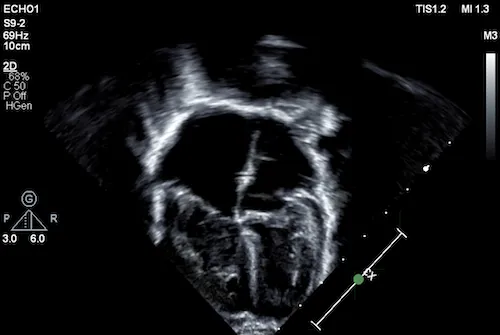

echocardiogram

The interpretation of a pediatric echocardiogram requires the expertise of a pediatric cardiologist. There is disparate access to such expertise worldwide, motivating our effort to create AI algorithms to bridge this gap by automating and standardizing echocardiogram measurements and interpretations. Such technology may also help improve clinician echocardiogram workflows in large centers such as Boston Children’s.

Although cardiac imaging gives clinicians perspectives of the heart that are immensely useful for diagnostics and treatment planning, there are still aspects that can escape the human eye. Thanks to AI, we can start seeing those unseen aspects. Our lab is also creating AI-enabled echocardiogram models that will help predict meaningful insights into heart structure and function that would potentially otherwise escape the trained eye. For example, while an ultrasound can clearly show the contraction, or squeeze, of the heart’s left side, it cannot reliably tell the squeeze or size of the right side. With AI, we’re aiming to reveal these metrics and many other undetectable characteristics of a child’s heart to enhance their care.